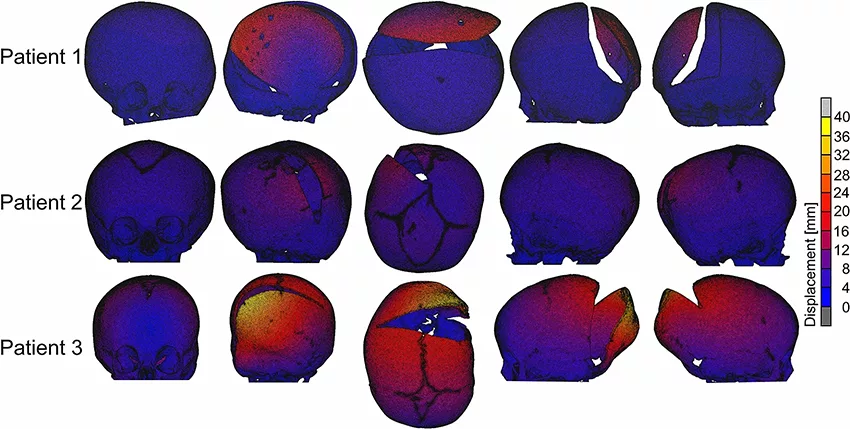

使用未受手术影响的前鼻棘点和额颧缝处标志点获得体积配准后,在 Simpleware CAD 模块对扩张的FE颅骨模型和术后 CT 重建颅骨进行表面偏差分析。然后通过调整参数以考虑每个模型中整个颅骨的平均负和正的表面偏差,使用热 FE 模型迭代地进行模拟。

重建的颅骨模型展示了术前 CT 时的颅内腔形态,对三名患者的模拟结果进行对比。FE 模型和从 CT 获得术后颅骨模型的分析显示额骨和颞骨的表面偏差率相对较低,在被弹簧扩张的后颅骨上表面偏差增大。